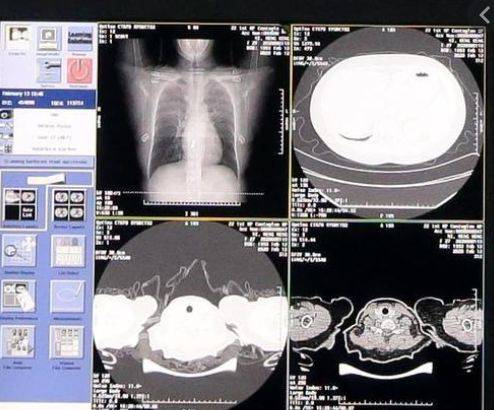

新加坡医生关于新冠肺炎的新发现

新冠肺炎初期病毒含量最高新加坡的医生最新发现:新冠肺炎初期病毒量最高,传染性或更强!大家都知道,新冠病毒非常狡猾,很多病患在染病初期症状都不明显,只不过出现咳嗽和发烧等一些轻微症状。

但实际上这个时候才是最危险的!因为此时病毒量最高!等到病毒进入肺部的时候,病症加强,其实病毒量已经显著减少!可见患者的病毒量与出现的症状并不成正比!

因此专家建议:一旦身体发生变化,哪怕只是出现轻微状况,也要戴口罩和看医生,除此之外也不要乱跑,尽量留在家中,以免传播病毒!卫生部卫生科学长陈祝全教授指出,这与SARS情况相反,SARS是随着病情加剧才产生更多病毒。而新冠病毒和流感都是初期病毒最多!

因为一切都来自于科学!就拿病毒量与病症的关系来说,新加坡的医疗团队做了大量的实验进行观察。这项观察源自本地针对冠病病患展开的研究,当局在本地疫情暴发后,马上招募病患,至今已有超过60人参与。